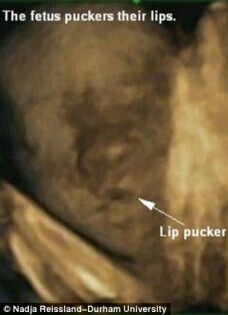

stirileprotv.ro Medicii au aflat ca miscarile pe care le au fetusii in pantecul mamei sunt un bun indicator al sanatatii micutilor, chiar dinainte de nastere.